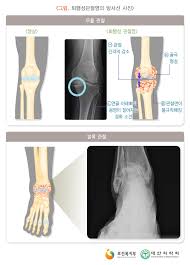

무릎 관절경수술

발목 관절경수술